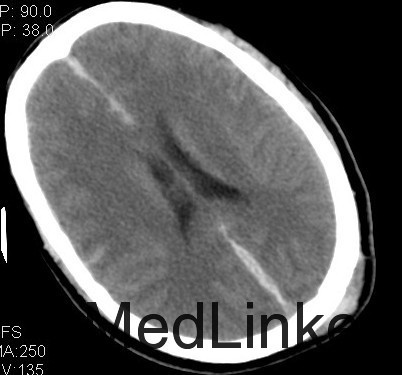

诊断:1、双侧额挫裂伤; 2、大脑镰、右侧额颞硬膜下出血;3、右额颞脑出血; 4、左枕骨骨折; 5、中枢神经系统感染 主要经过:入院后完善术前相关检查,行右侧额颞脑挫裂伤清除+去骨瓣减压+颅内压探头置入术;后行左侧额叶血肿清除+额颞顶去骨瓣减压术,术后予以抗感染、营养神经、改善循环、化痰、护胃、抗癫痫及营养支持治疗。 术后复查CT:双侧额颞顶骨局部缺如;左侧枕骨不连。 双侧额颞顶部皮下软组织稍肿胀。双侧额叶软化灶;右侧额颞部硬膜下及大脑纵裂池积液;右侧额颞部少量积气

随访+诊断:脑挫裂伤是指暴力作用于头部,造成脑组织的器质性损伤。包括挫伤和裂伤两种病理类型。它是颅脑损伤后在大体解剖和CT上最常见的一种损伤,通常为多发并伴有其他类型的颅脑损伤。脑挫裂伤可发生于受暴力直接作用的相应部位或附近,产生冲击伤,但是通常发生严重和常见的是脑挫裂伤出现在远离打击点的部位,暴力作用点的对应点,产生严重的对冲伤。由于颅骨骨折,开放性损伤容易发生颅内感染,应尽早手术治疗。